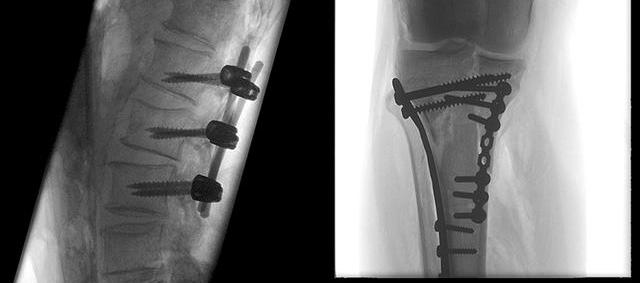

旗下的PLX7200型移動式三維C型臂等產品在市場獲得了良好口碑,能夠提供術中3D成像,適用于骨科、外科、矯形外科、泌尿外科、脊柱外科、腹部外科、疼痛科、消化科、婦科及手術室等,大幅度拓寬骨科手術范圍,提高診治水準。支持骨組織活檢、脊柱椎弓根螺釘植入術、長管狀骨髓內釘固定術、及適合采用螺釘固定的手、足骨折手術等骨科、創傷科復雜診治。